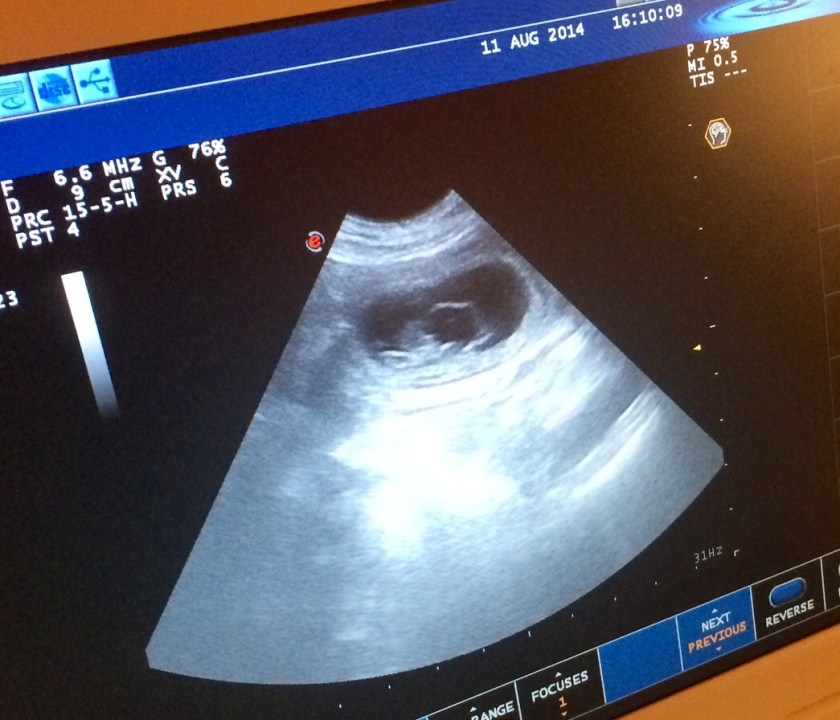

Vi har vært på ultralyd…

og gleden er stor, for det viser seg at Bitten er drektig! Undersøkelsen viste at hun venter et middels stort kull, antakelig 4-6 valper 🙂

Det er fortsatt mye som kan gå galt, men Bitten er frisk og fin, så vi krysser fingrene og fortsetter nedtellingen til termin, som blir rundt 15. september.

Fostrene er nå omtrent 1,7 cm lange, og man kan se fosterposer og små hjerteslag 🙂 Her kommer noen bilder fra ultralydundersøkelsen. Fotograf er Tommy Bratteng.